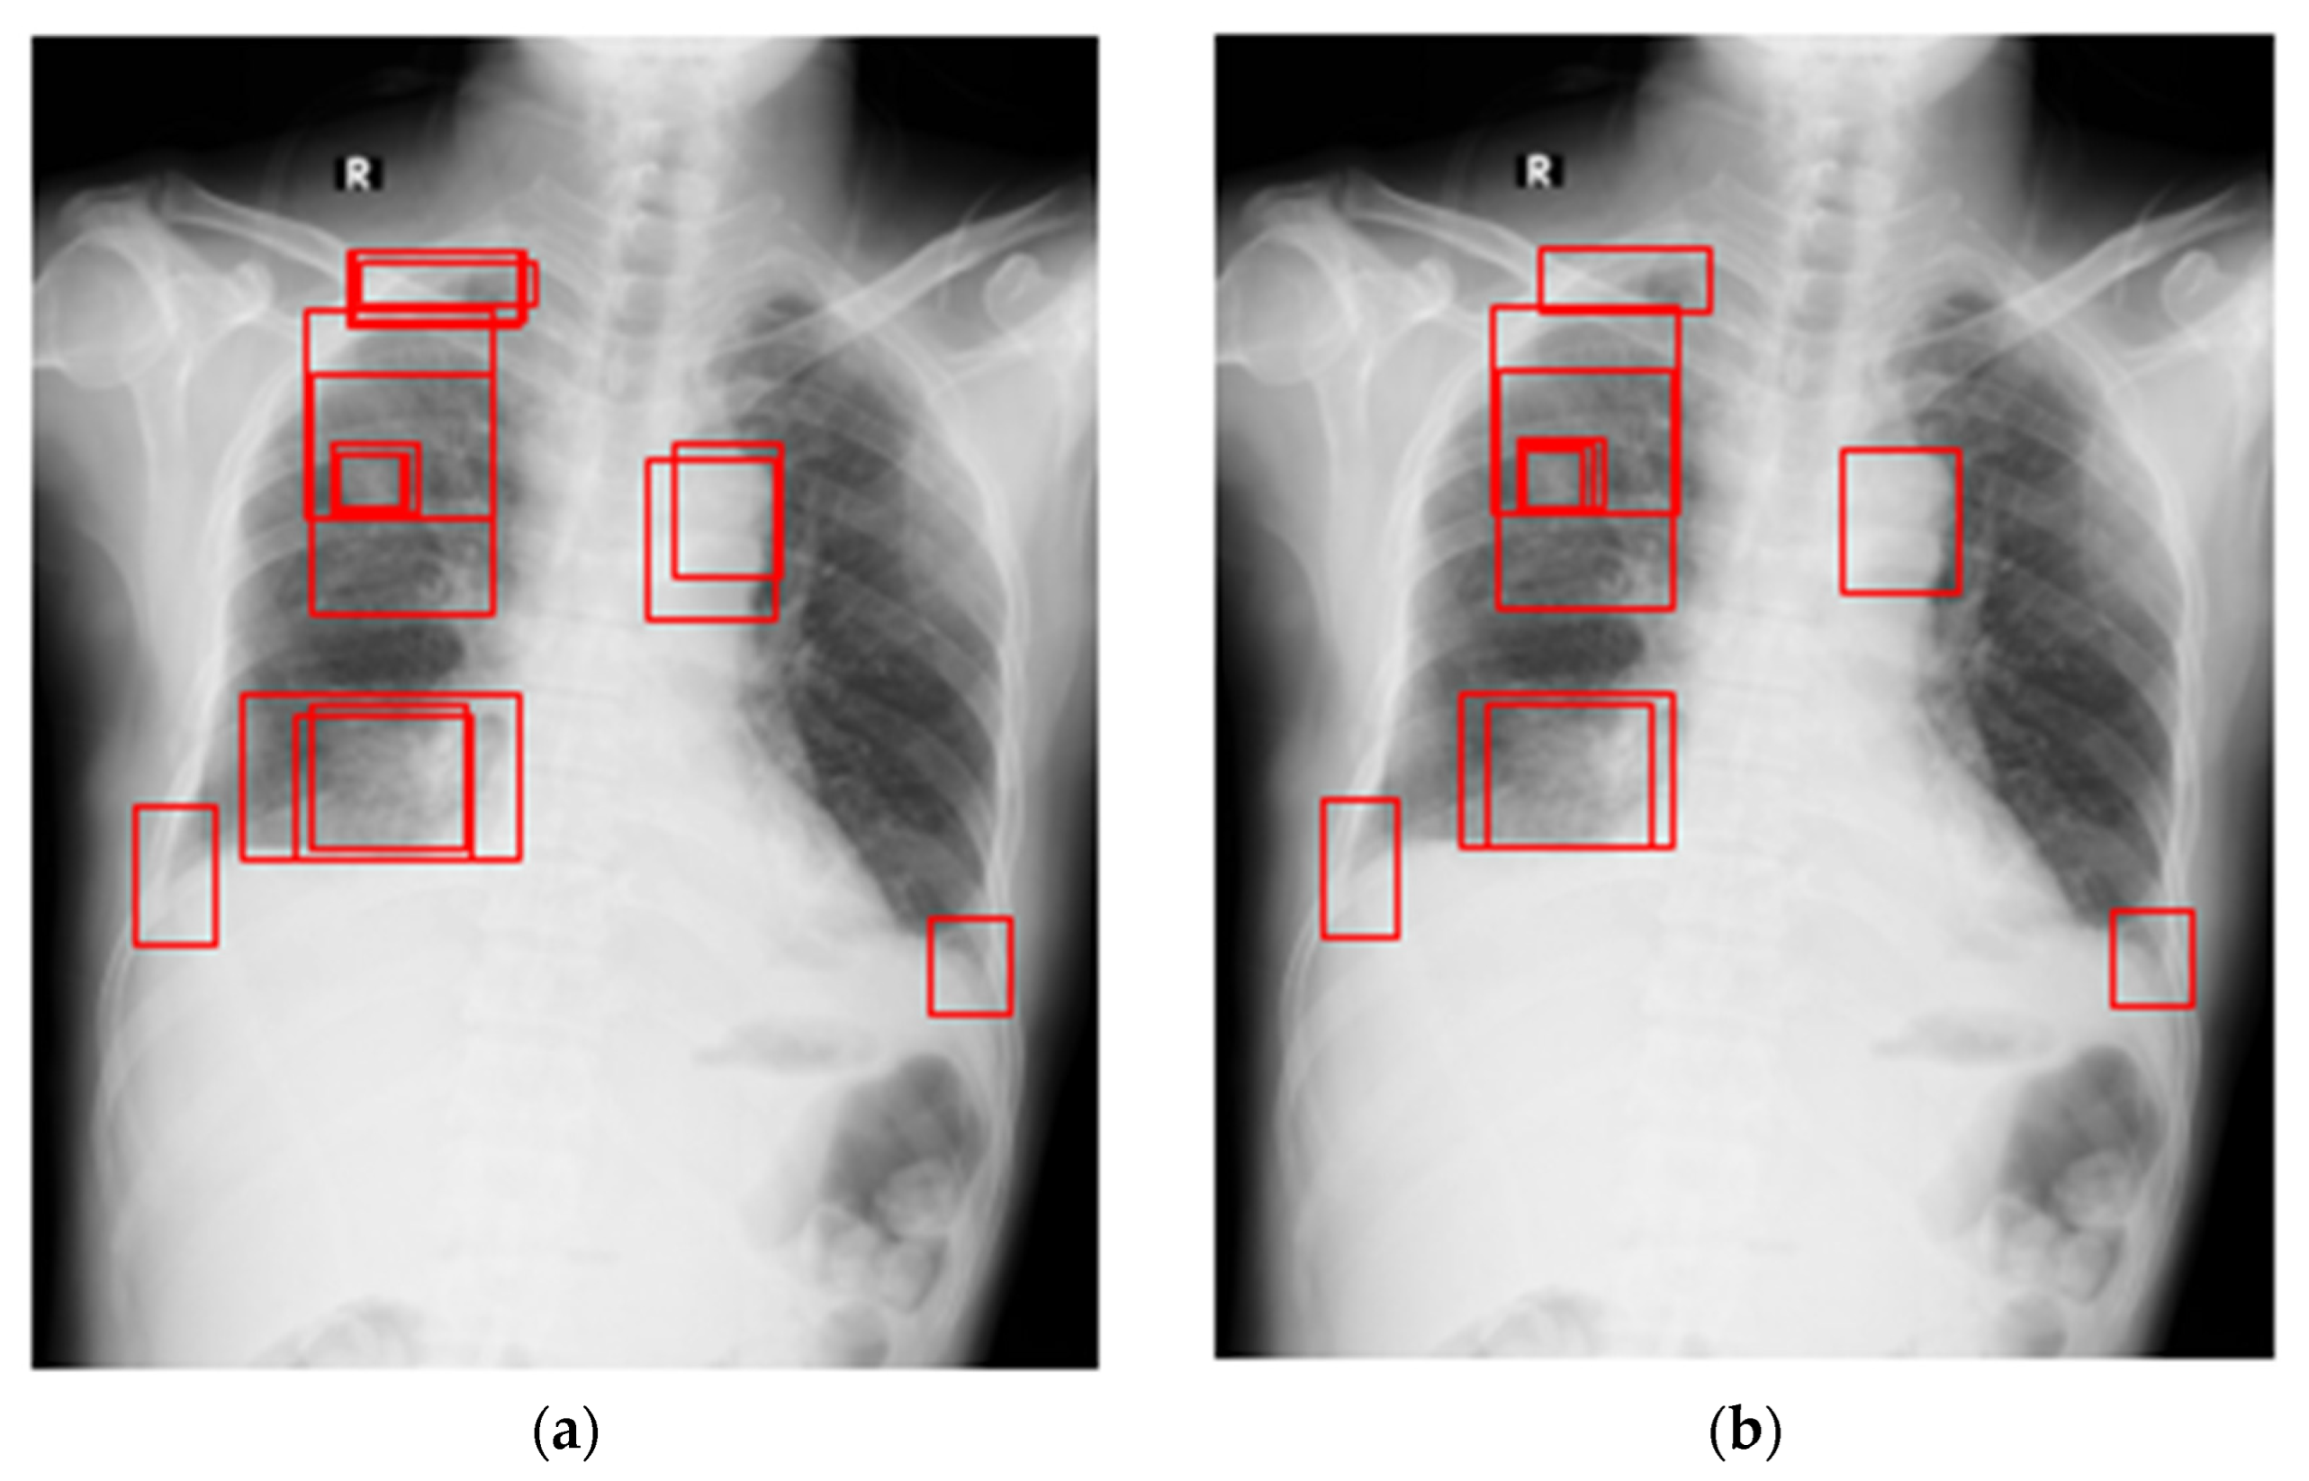

4.1. Experimental Datasets and Pre-Processing